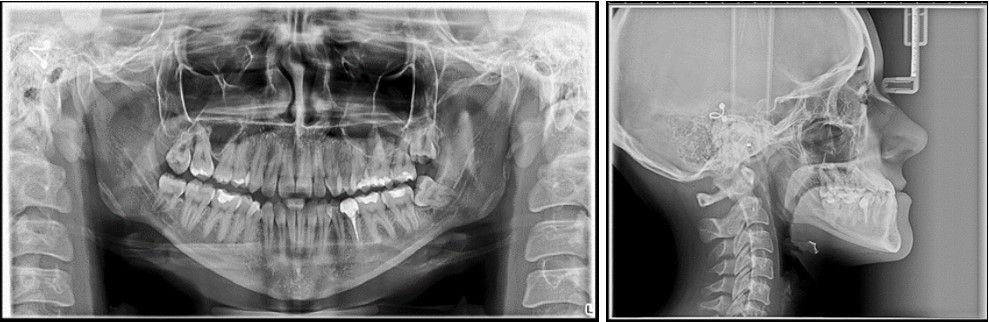

The panoramic radiograph examination showed impacted bilateral mandibular third molars, and one maxillary third molar.Cephalometric analysis disclosed a skeletal class III (ANB -5 degrees), with a retruded maxilla and a protruded mandible (SNA 78 degrees and SNB 83 degrees). The patient is a hyperdivergent type, with FMA 30 degrees and IMPA 77 degrees, which suggests retruded lower incisors. Examination of soft tissue on the profile radiograph shows a concave profile and a protruded lower lip. (Figure 3).

Figure 3.Initial panoramic and lateral cephalometric radiographs